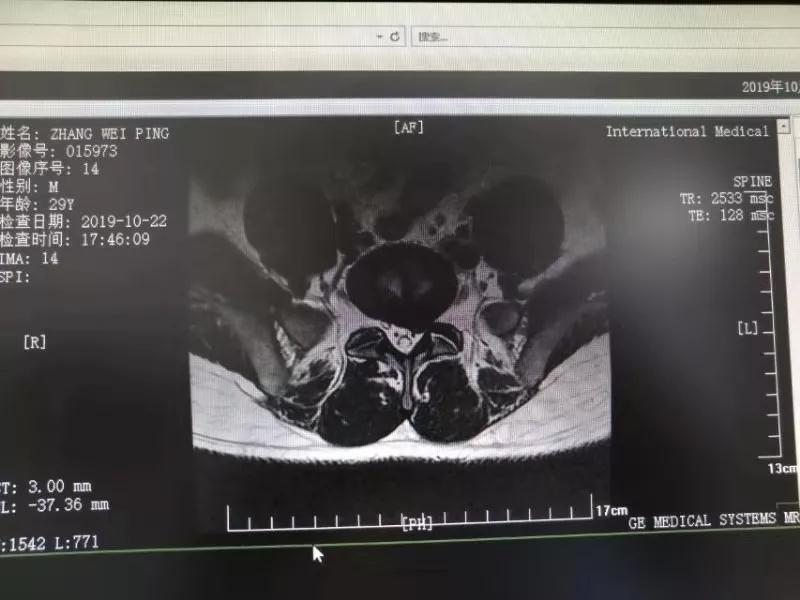

10月25日,29歲的患者小張了解到西安國際醫(yī)學(xué)中心骨科醫(yī)院專家云集,一大早便在家人的陪同下,來到西安國際醫(yī)學(xué)中心骨科醫(yī)院就診?!拔已闯掷m(xù)2年多,最近感冒后腰痛癥狀明顯加重了。”小張面露苦楚,因為長期腰痛、左下肢放射性疼痛,她晚上睡覺不能平躺,經(jīng)常疼得睡不著,需要口服止痛藥物才能有所緩解。走路走不了多遠(yuǎn)就開始腿抽的疼,嚴(yán)重影響到工作和生活。

結(jié)合患者的檢查以及年齡情況,王自立副院長推薦讓專門研究椎間孔鏡技術(shù)王雄勛主任給小張做微創(chuàng)的椎間孔鏡手術(shù)。該手術(shù)創(chuàng)傷很小,不影響脊柱的穩(wěn)定性,尤其適合于椎間盤突出的年輕患者,懷著對骨科醫(yī)院專家的信任,小張與家人商議后,接受手術(shù)治療。